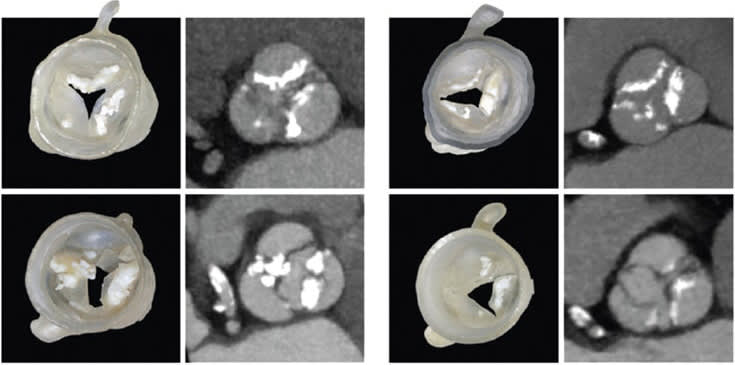

To solve that problem, Ahmed Hosny, who was a research fellow at the Wyss Institute at the time, created a software program that uses parametric modeling to generate virtual 3D models of the leaflets using seven coordinates on each patient's valve that are visible on CT scans. The digital leaflet models were then merged with the CT data and adjusted so that they fit into the valve correctly. The resulting model, which incorporates the leaflets and their associated calcified deposits, was then 3D printed into a physical multimaterial model.

The team also 3D printed a custom “sizer” device that fits inside the 3D printed valve model and expands and contracts to determine what size artificial valve would best fit each patient. They then wrapped the sizer with a thin layer of pressure-sensing film to map the pressure between the sizer and the 3D printed valves and their associated calcified deposits, while gradually expanding the sizer.

In addition, the multi-material design of the 3D printed valve models, which incorporate flexible leaflets and rigid calcified deposits into a fully integrated shape, could much more accurately mimic the behavior of real heart valves during artificial valve deployment, as well as provide haptic feedback as the sizer is expanded.